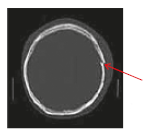

• Skull fracture

There are two types of skull fracture:

• Undisplaced skull fracture is caused by a direct impact to the skull which causes it to break with no shattered fragments. No surgical treatment is required as the bone will heal by itself.

• Depressed skull fracture is caused by a direct impact to the skull which causes the shattered bones to be pushed into the brain (Figure 1). Antibiotics and surgery may be needed to prevent further brain injury, bleeding and infection.

Depressed skull fracture

Figure 1